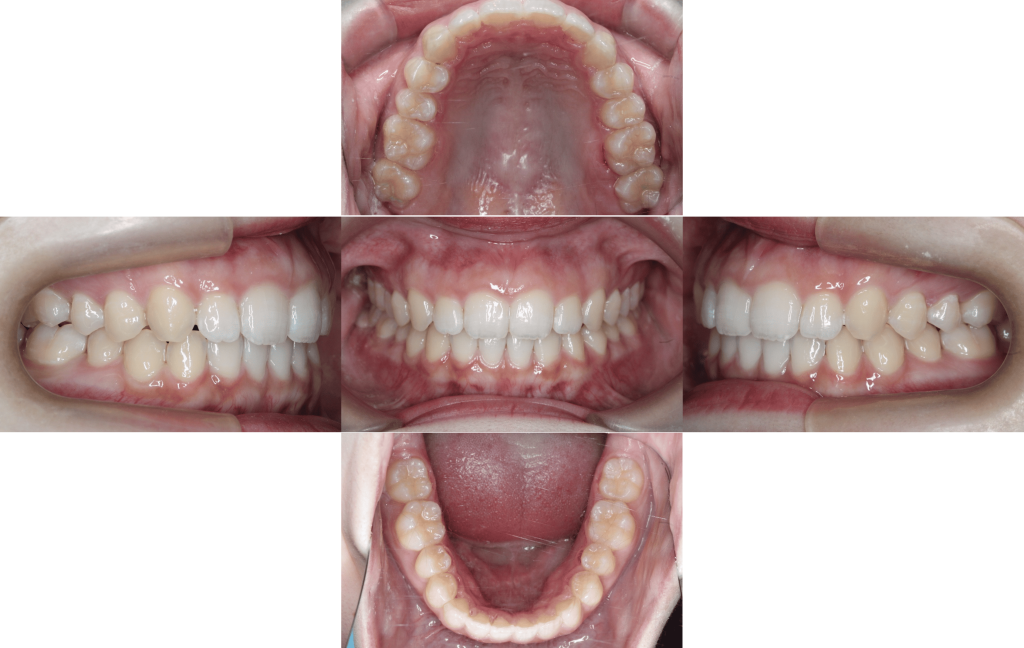

Before

初診